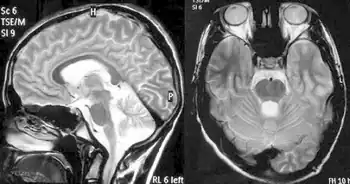

Friedreich's ataxia-MRI of brain showing cerebellar atrophy[24]

Balance difficulty, loss of proprioception, an absence of reflexes, and signs of other neurological problems are common signs from a physical examination.[10][25] Diagnostic tests are made to confirm a physical examination such as electromyogram, nerve conduction studies, electrocardiogram, echocardiogram, blood tests for elevated glucose levels and vitamin E levels, and scans such as X-ray radiograph for scoliosis.[26] MRI and CT scans of brain and spinal cord are done to rule out other neurological conditions.[27] Finally, a genetic test is conducted to confirm.[27]